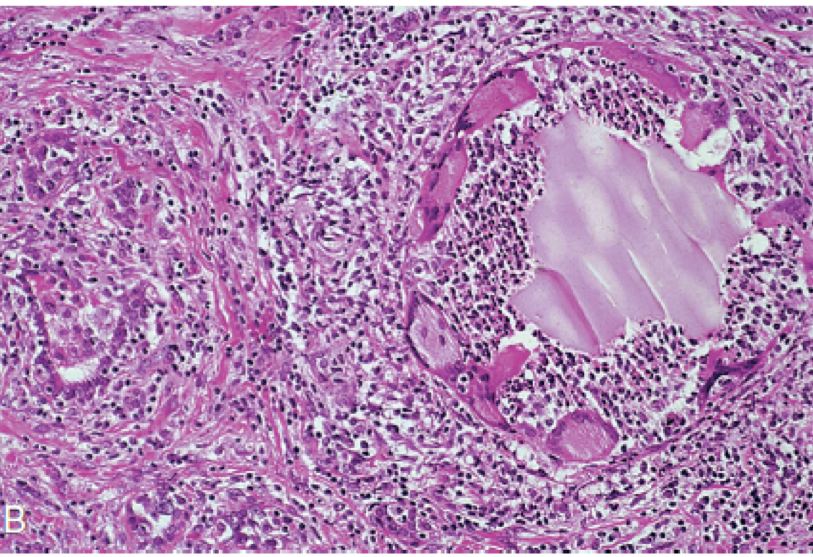

Thyroïde, douleur exquise à la palpation.

Quel est votre diagnostic ?

Thyroïdite granulomateuse subaigue ( thyroïdite de De Quervain)

Quel est votre diagnostic?

Thyroïdite de palpation (thyroïdite granulomateuse multifocale)